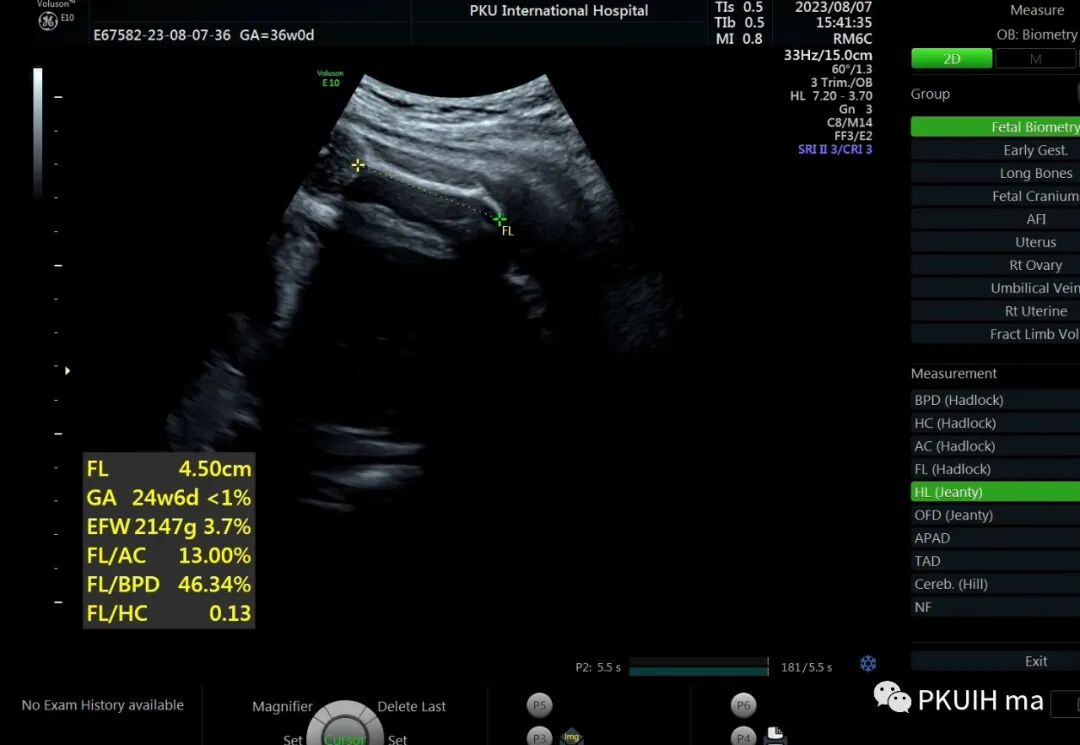

36周检查发现肢体越来越短,股骨和肱骨只相当于25-6周

头围双顶径已经大于相对孕周了,明显的头大肢体短。足底长度正常范围。